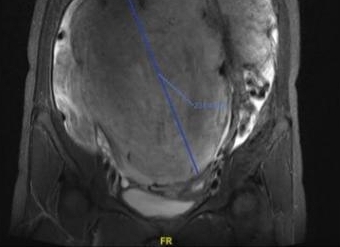

年轻少妇腹大如十月怀胎,结果却是长了巨大肿瘤。日前,一名患有巨大阔韧带肌瘤的患者在上海第九人民医院妇产科接受手术治疗,康复出院。